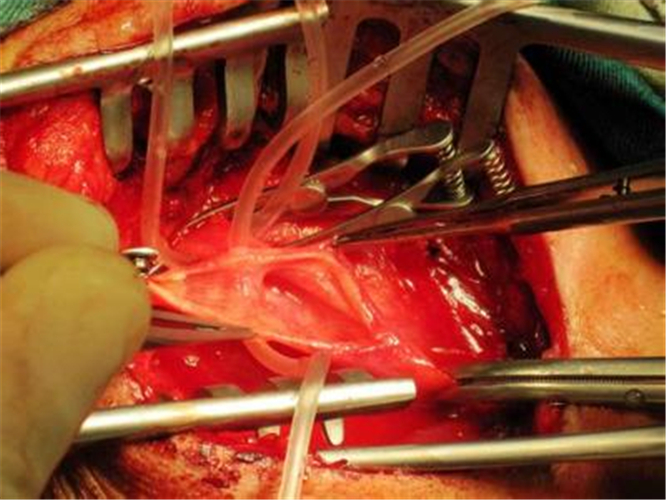

治療腦梗塞手術

治療急性期缺氧性腦梗塞

小腦腦梗塞手術

手術治療腦梗塞的

手術治療腦梗塞